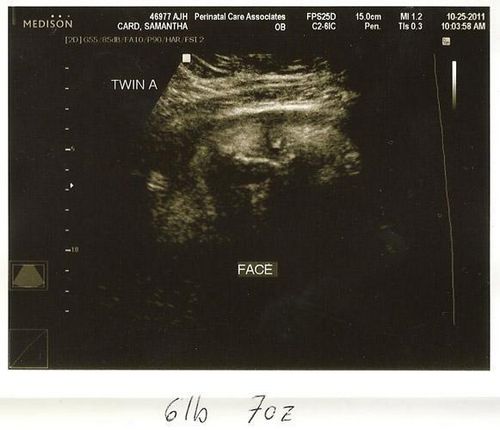

На 36 тижні вагітності фото дитини може бути зроблено в період, коли він не спить і мама зможе розгледіти, що його щоки округлилися і він значно виріс. Всі органи малюка повністю сформувалися, триває розвиток нервової системи і зміцнюються кістки. Обов'язково треба, щоб мама була морально готова до пологів, якщо вагітність багатоплідна або пізня. Тому що в цьому випадку 36 тиждень вагітності, фото якої зроблять в медичному центрі при обстеженні, може стати першим тижнем життя малюка або малюків.